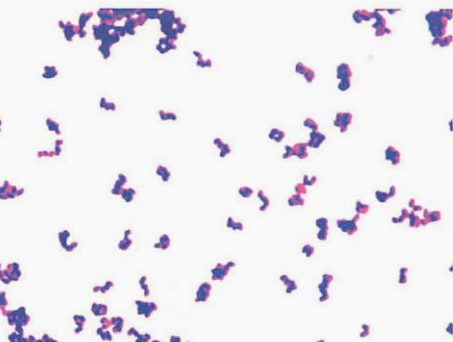

革兰阳性杆菌,V形、栅栏状,单个或成双排列(图 6)。痰标本直接涂片查见革兰阳性杆菌(图 7)。血培养阳性培养物直接涂片查见革兰阳性杆菌(图 8)。

图 6纹带棒杆菌在血琼脂平板上纯培养镜下形态(革兰染色)

图 8 含树脂血培养瓶涂片(革兰染色)